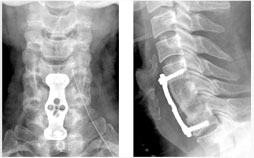

전방 요추체간 유합술 (Anterior Lumbar Interbody Fusion)

- 수술시 출혈이 적다.

- 수술 창상이 적다

- 수술 후 조기보행이 가능

- 수술 후 인접 척추체에 영향이 적다